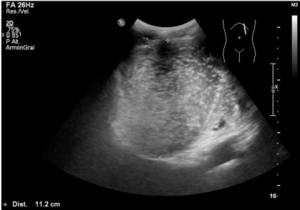

Junto con la radiografía simple de abdomen, la ecografía es el método de elección para el estudio de las patologías del aparato digestivo y genitourinario, siendo una técnica barata, disponible prácticamente en todos los centros y no invasiva, la cual no produce radiación ionizante. Por la sintomatología del paciente, en este caso, sería la prueba de elección.

¿Qué hallazgos patológicos encontramos en la ecografía?